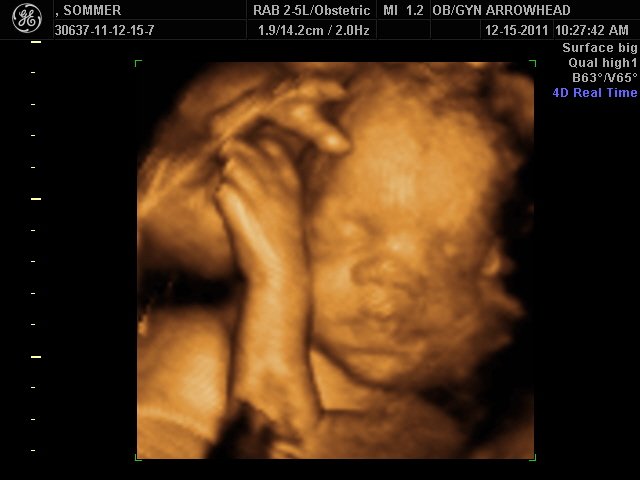

We offer complimentary 3D/4D Ultrasounds to all our OB patients around 30 weeks! The following photos are some examples of our work, shown with permission from our patients.